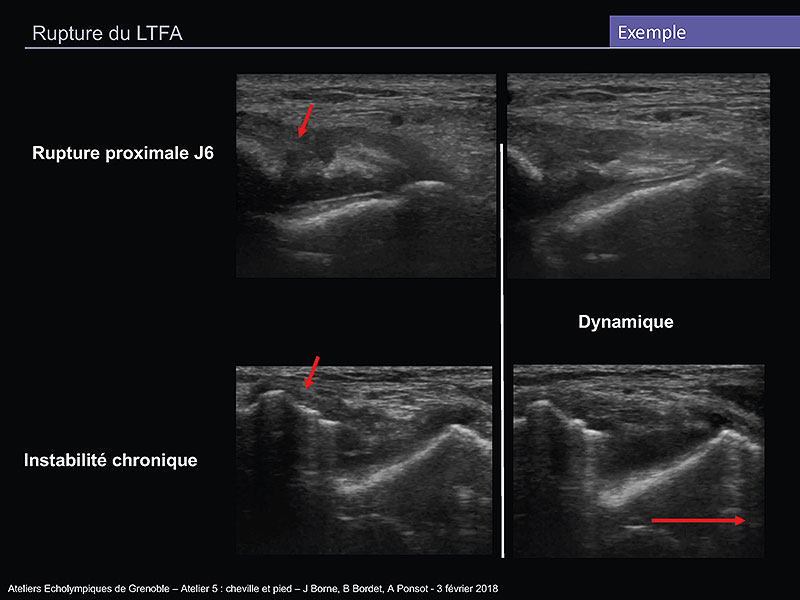

Membre inférieur distal traumatique et sportif

B. Bordet, J. Borne, A. Ponsot